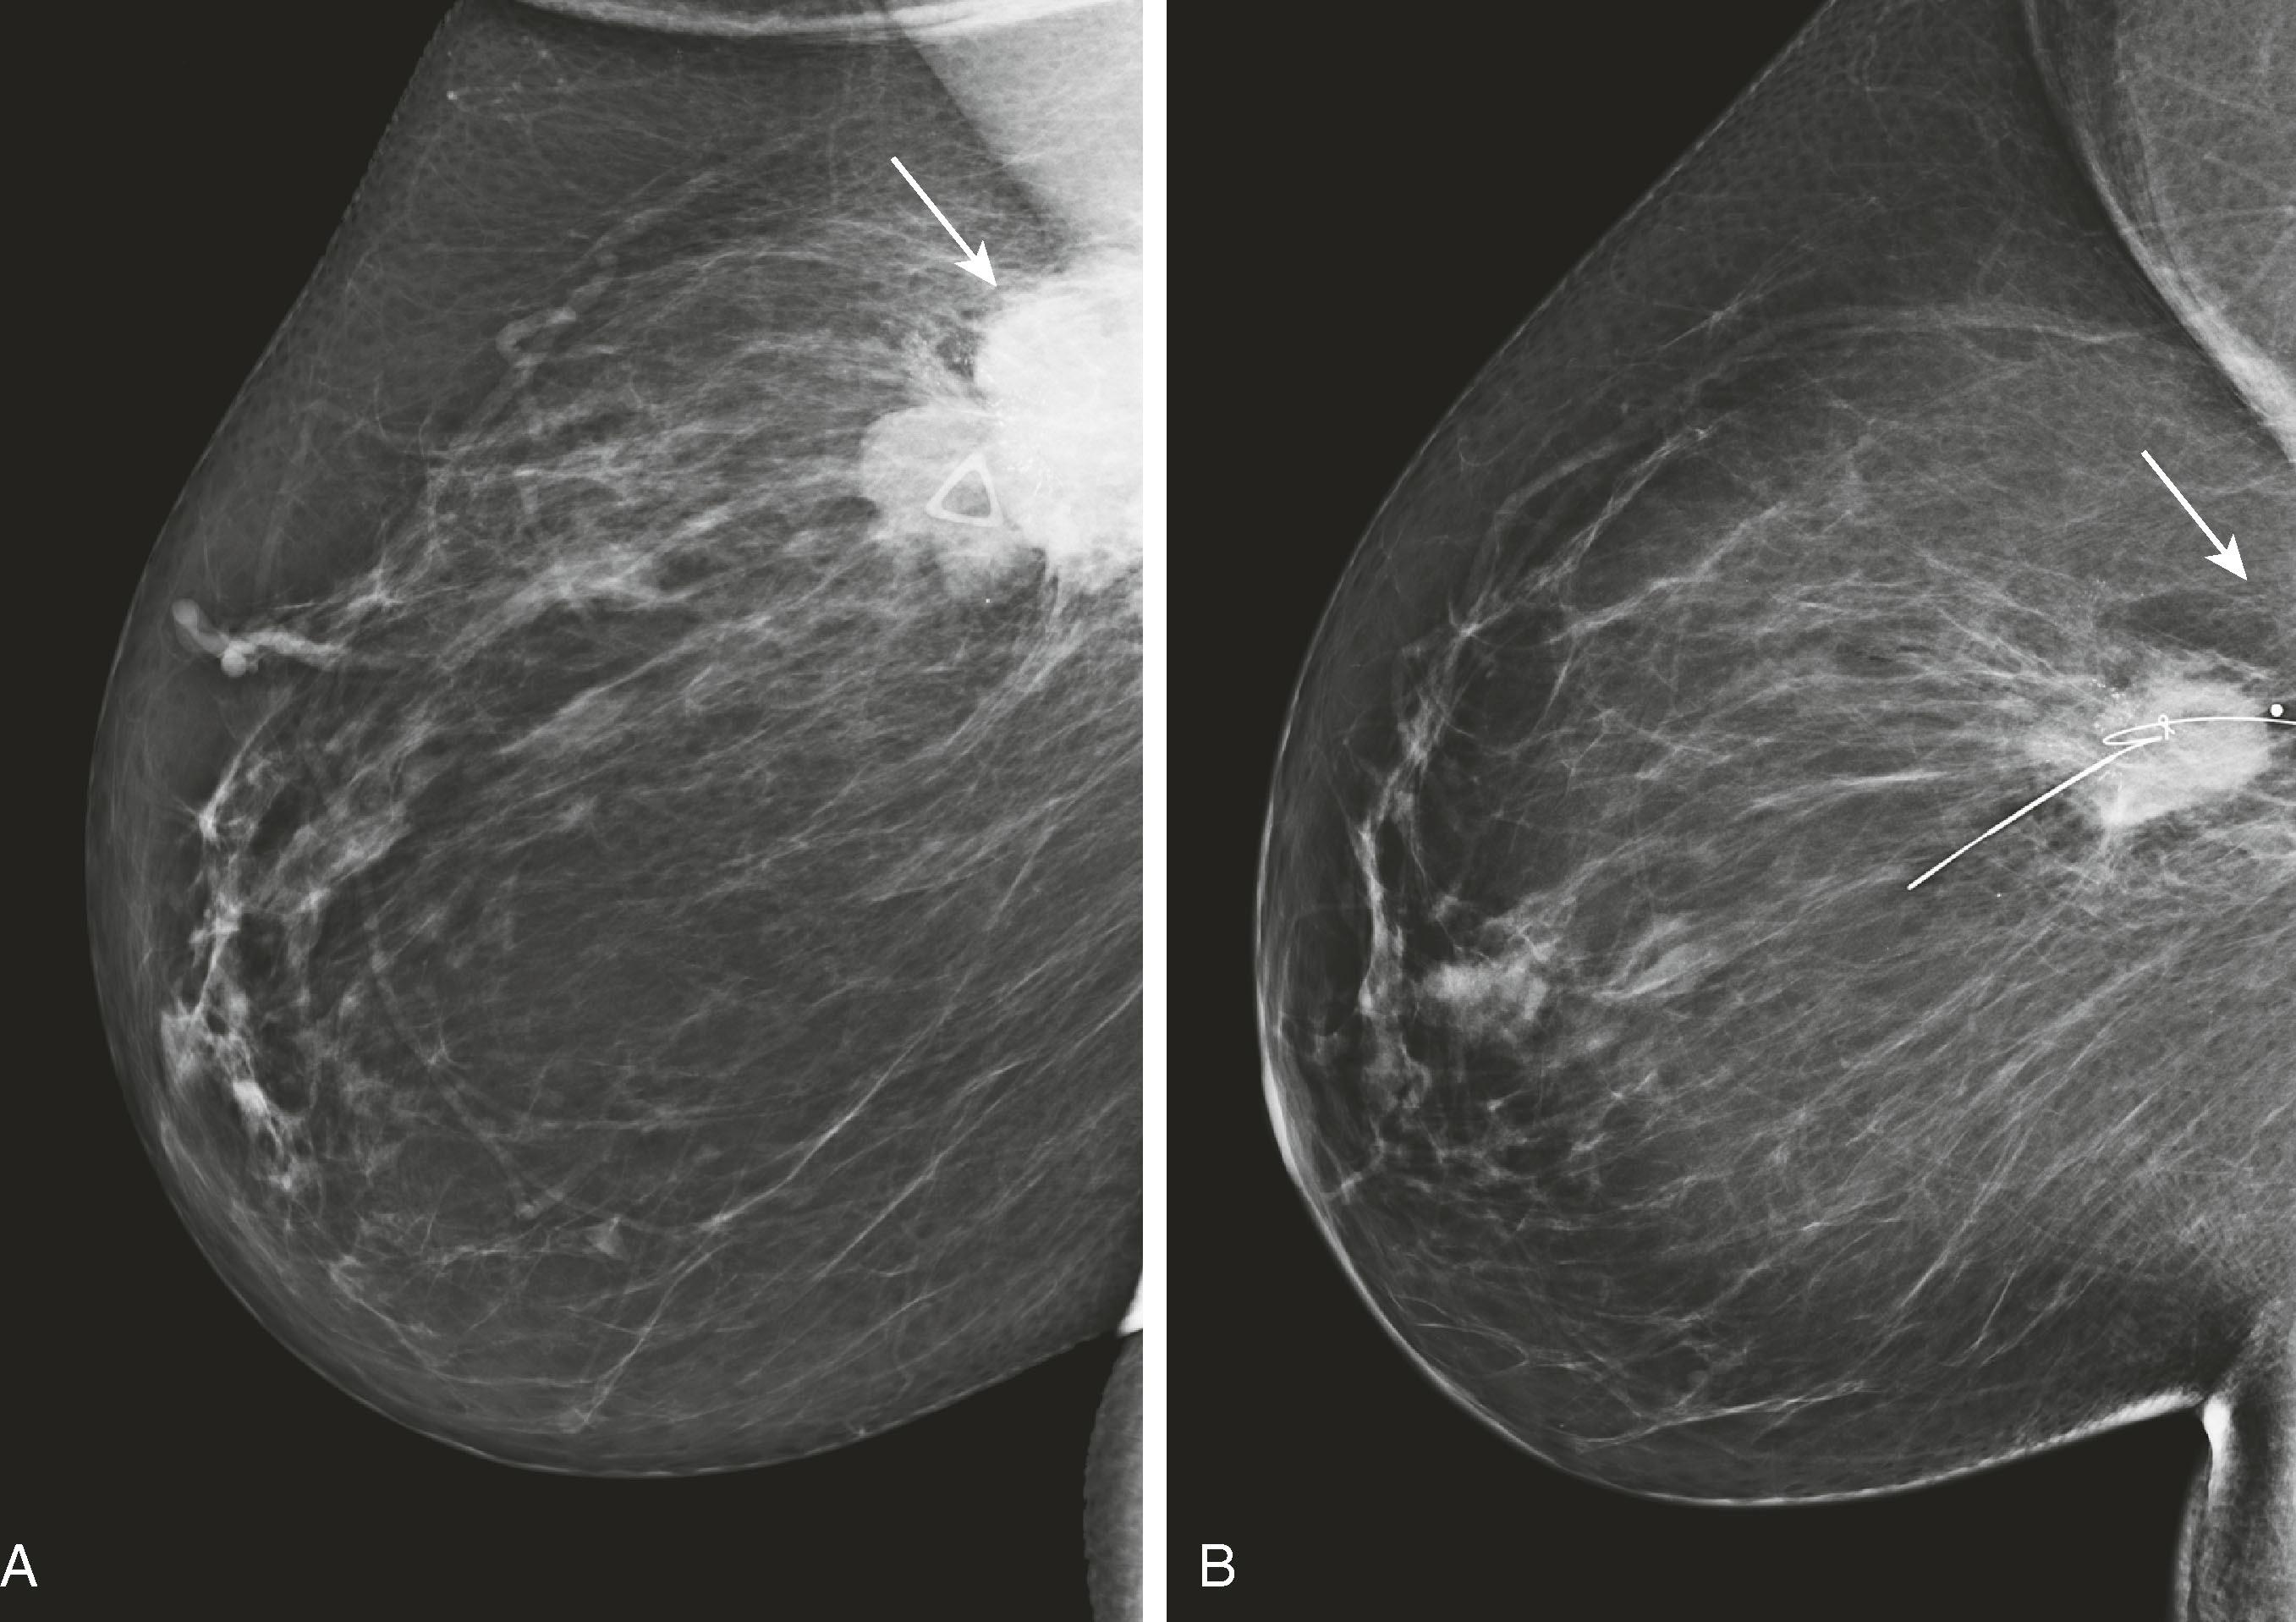

Mammography is important not only in the diagnosis of breast cancer but also in the surveillance and assessment of neoadjuvant chemotherapy ( Fig. 8.10 ).

Fig. 8.10, An oblique view before ( A ) and after ( B ) 8 months of neoadjuvant chemotherapy ( arrows mark the known carcinoma, shown to be smaller after neoadjuvant chemotherapy). This allowed for improved cosmesis after a smaller lumpectomy. ( B ) contains the localizing wire.

MRI is useful for following the response of tumors to neoadjuvant chemotherapy . Mammography, ultrasound, and physical examination are notoriously inaccurate in evaluating the response to chemotherapy. MRI and PET have proved to be superior in this regard. Kuhl reported that MRI findings have been shown to correlate better with tumor response than conventional imaging, with correlation coefficients ranging between 0.72 and 0.93 versus 0.30 and 0.52. One important caveat is that MRI, although very sensitive for detecting macroscopic invasive cancer, cannot exclude residual microscopic disease or low-grade DCIS. Although the MRI appears negative, there may be tumor remnants in 30% of patients. Interestingly, the underestimation is greater for patients who have a complete MRI response to chemotherapy than for patients who have a partial or no response. Fig. 8.31 demonstrates a complete MRI response to chemotherapy in a patient with lobular carcinoma. Fig. 8.32 demonstrates a patient with a partial response to chemotherapy. The tumor diminished in size with only several residual foci of tumor, and the kinetic pattern changed from plateau to progressive.

Fig. 8.31, Patient with a history of lobular carcinoma ( solid arrow in A ) and enlarged right axillary lymph nodes ( open arrow in B ). After the administration of neoadjuvant chemotherapy, all magnetic resonance imaging evidence of the tumor ( solid arrow in C ) and lymphadenopathy ( open arrow in D ) disappears.

Fig. 8.32, ( A ) Invasive ductal carcinoma in the left breast (arrow) before chemotherapy. ( B ) After chemotherapy, there is a partial response. The tumor is smaller (arrow) , and the washout pattern has changed from plateau to progressive.